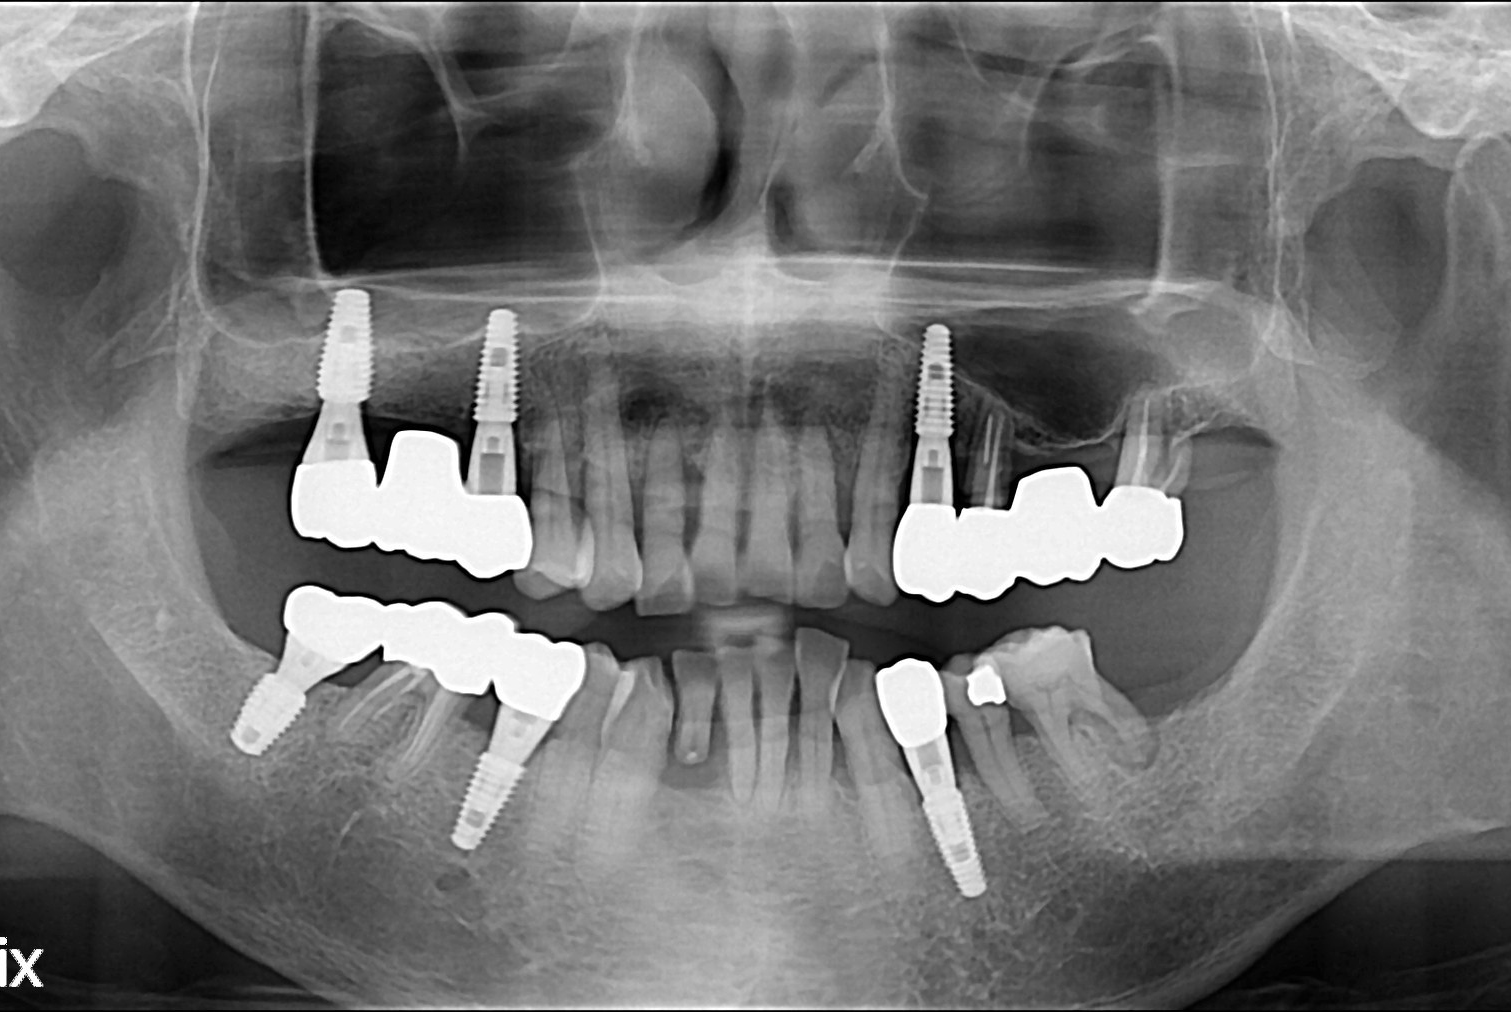

치료후 : 2017-06-28

세종치과는 많은 환자와 다양한 케이스를 바탕으로 항상 편안한 임플란트 수술을 제공하고자 노력하고,

오래동안 튼튼히 쓸 수 있는 임플란트 수술을 가장 큰 목표로 삼고 있습니다